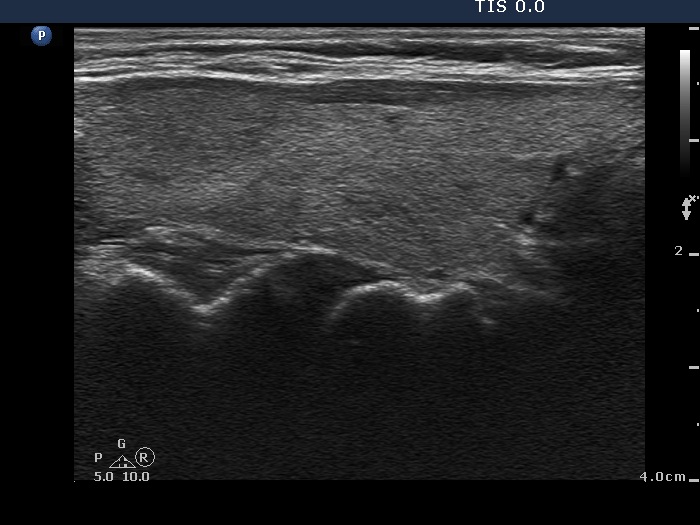

Intranodular hyperechogenic figures - case 1789 (ultrasonographic picture 2)

Right lobe, longitudinal view.